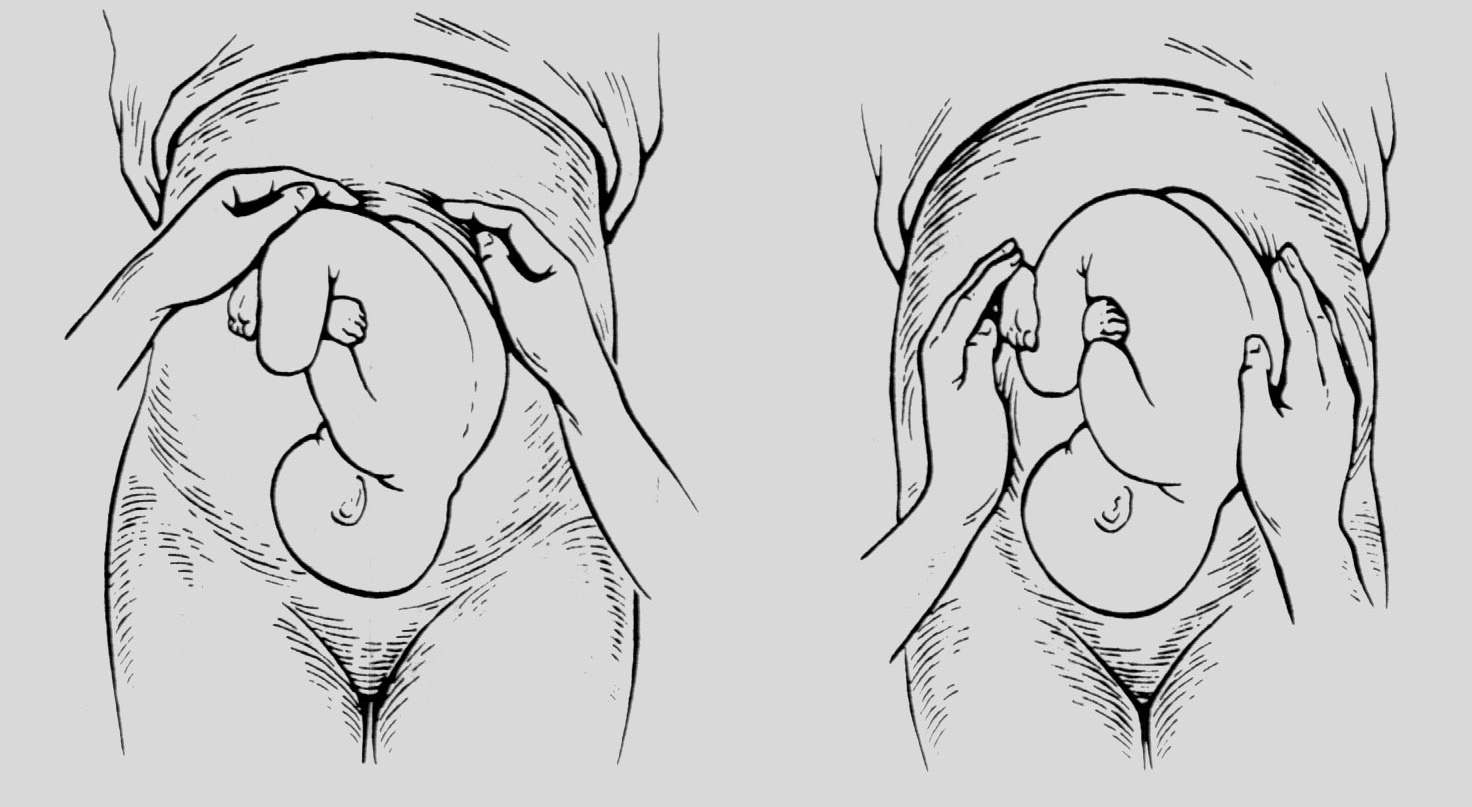

Наружное акушерское исследование приемы Леопольда Левицкого

Третий прием Леопольда-Левицкого

Приемы наружного акушерского исследования Леопольда Левицкого

Второй прием Леопольда-Левицкого определяет

Приемы наружного акушерского исследования Леопольда Левицкого